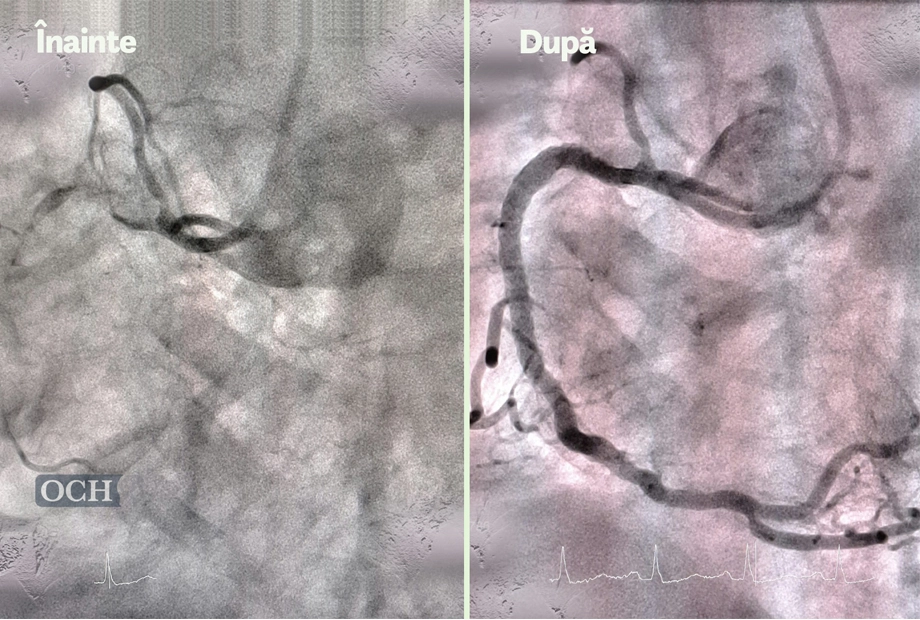

Sfaturi și sugestii pentru pacienții OCH

despre Ovidius Clinical Hospital.